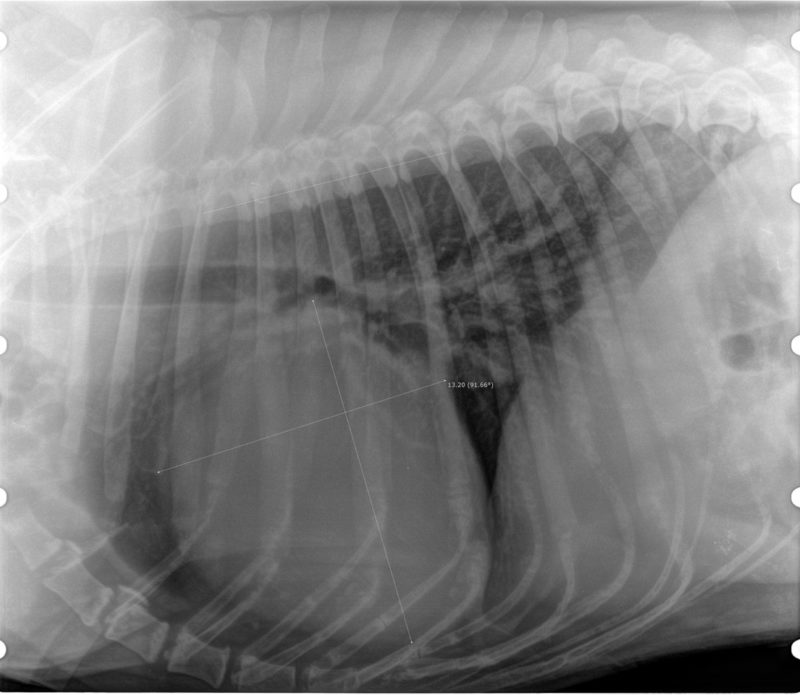

Eine angefertigte Röntgenaufnahme des Brustkorbes im seitlichen Strahlengang lieferte uns den ersten Beweis. Das Herz war riesengroß, durch die Ausdehnung des Herzens wird die Luftröhre mit den Hauptbronchien zur Wirbelsäule gedrängt und eingeengt. Das ist ein möglicher Grund für den Husten unserer herzkranken Hunde. Wir haben das Herz vermessen, die Längsachse und die Querachse des Herzens werden nach bestimmten Vorgaben auf die Länge der Brustwirbelkörper umgerechnet. Bei Faust ergab sich eine Größe von 13,2 Wirbelkörpern, normal ist ein Wert von 9-10,5, mit rassebedingten Schwankungen.